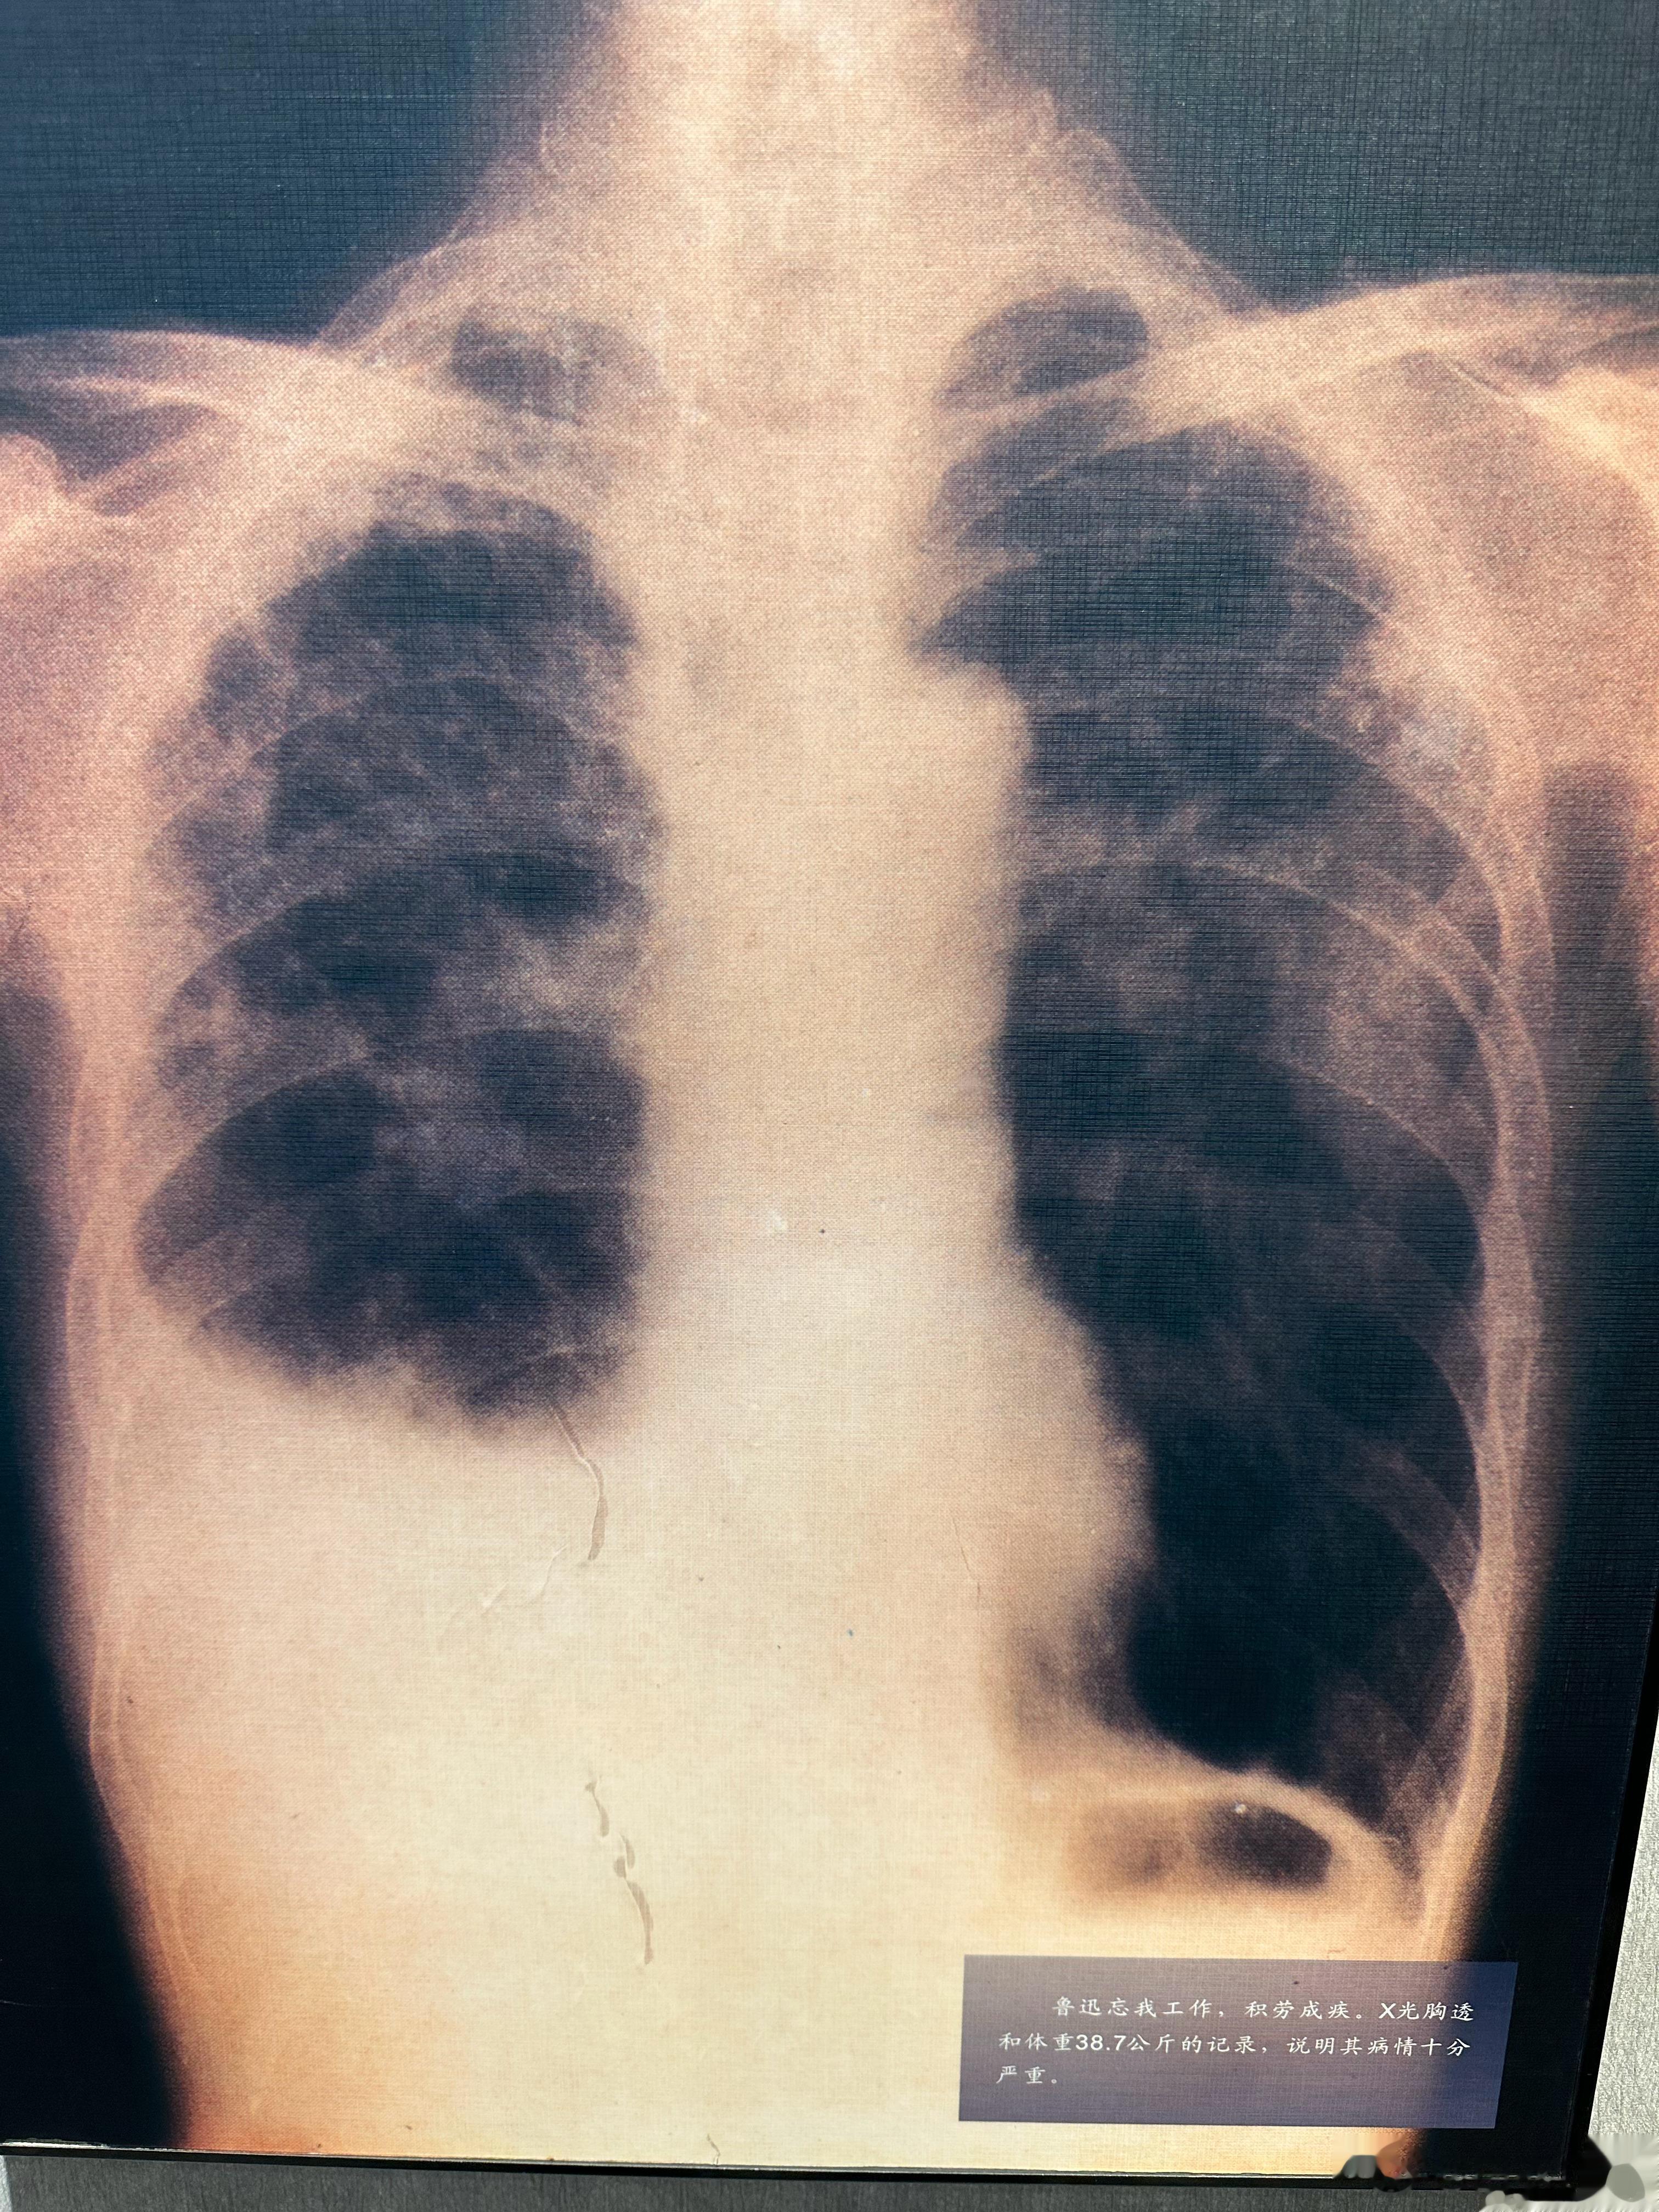

在鲁迅纪念馆,看到了鲁迅先生生前的胸片。一开始,我很奇怪,先生的纵隔和心脏怎么会